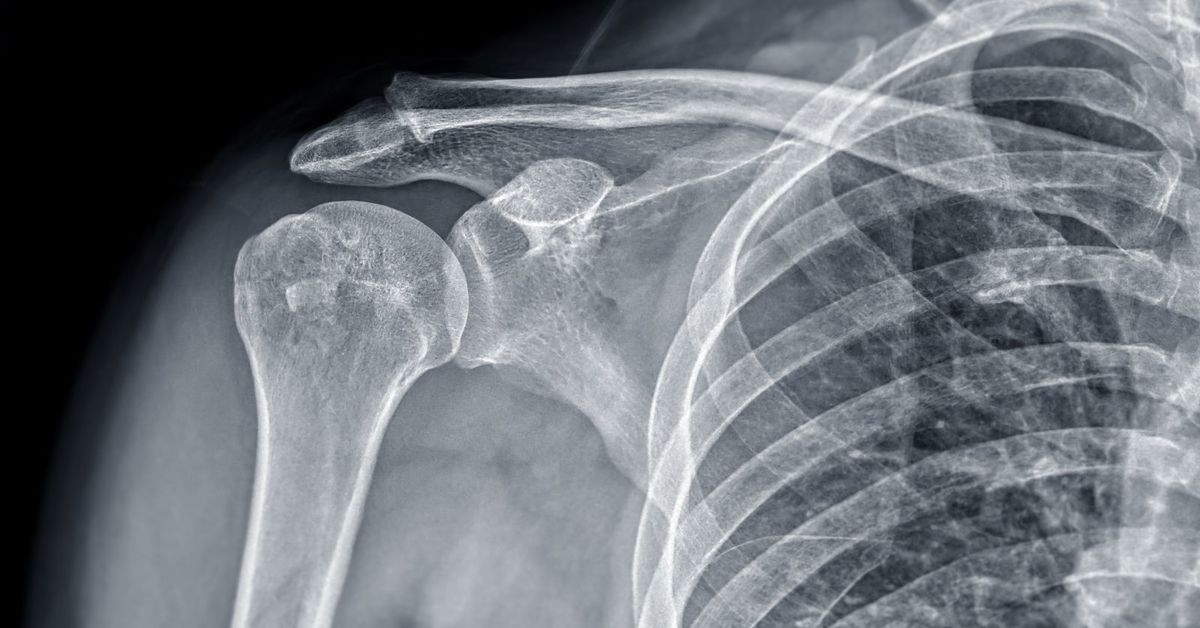

Etkilenen bölgede ilk başta hafif olan ve zamanla şiddetlenen bir ağrı hissedilir. Ağrı, genellikle aktiviteler sırasında artar ve dinlenmeyle azalır. Kırığın bulunduğu bölgede hafif bir şişlik meydana gelir. Kemik üzerindeki baskıya karşı hassasiyet artar. Bu bölgede dokunulduğunda ağrı hissedilir. Nadiren de olsa ciltte hafif renk değişiklikleri gözlemlenebilir. Zamanla yaralanma bölgesindeki ağrı, günlük aktiviteleri gerçekleştirmeyi zorlaştırabilir. Hareket kısıtlılığı yaratabilir. Stres kırığı belirtisi fark edildiğinde, profesyonel bir değerlendirme ve tedavi gerekir.

Stres kırığı olan bölgeyi iyileştirmek için birkaç hafta boyunca dinlenmek en temel tedavi yöntemidir. Etkilenen bölgeye aşırı yüklenmekten kaçınılmalıdır. Ağrıyı ve şişliği azaltmak için günde birkaç kez buz uygulaması yapılabilir. Ayak veya bacakta varsa, uygun destek sağlayan ayakkabılar veya özel ortopedik cihazlar kullanılır. Kasları güçlendirmek ve esnekliği artırmak amacıyla fizyoterapist eşliğinde egzersiz programı uygulanır.